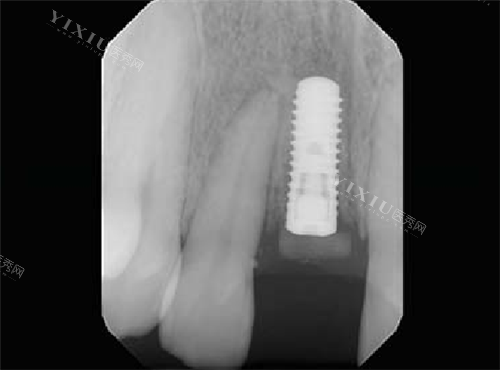

瑞锆种植体在应对骨量不足或复杂口腔状况方面表现出色。其采用的SLActive亲水表面处理技术能够显著促进骨细胞的生长和附着,即使在骨量不足的情况下也能实现良好的初期稳定性。这项技术通过改变种植体表面特性,使骨组织能够更快地与种植体结合,为骨整合创造有利条件。

此外,瑞锆种植体还适用于需要即刻种植的复杂病例。即刻种植对种植体的初期稳定性要求极高,而瑞锆种植体凭借其特殊设计和表面处理技术,能够在拔牙后立即植入,缩短整体治疗周期,同时保持良好的功能结果。

高稳定性是瑞锆种植体的另一大特点。即使在骨质条件不理想的情况下,其特殊表面处理也能确保种植体与骨组织形成牢固结合。这种稳定性不仅体现在初期固定阶段,更延续到长期使用过程中,为患者提供持久的咀嚼功能和舒适体验。